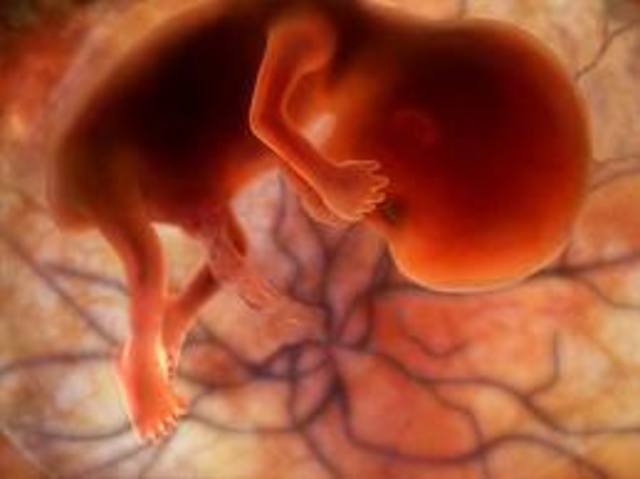

• Week 13

Week 13

The fetus can swim about quite vigorously. It is now more than 7 cm in length.

• Week 14

Week 14

The eyelids are fused over the fully developed eyes. The baby can now silently cry, since it has vocal cords. It may even start sucking its thumb. The fingers and toes are growing nails.